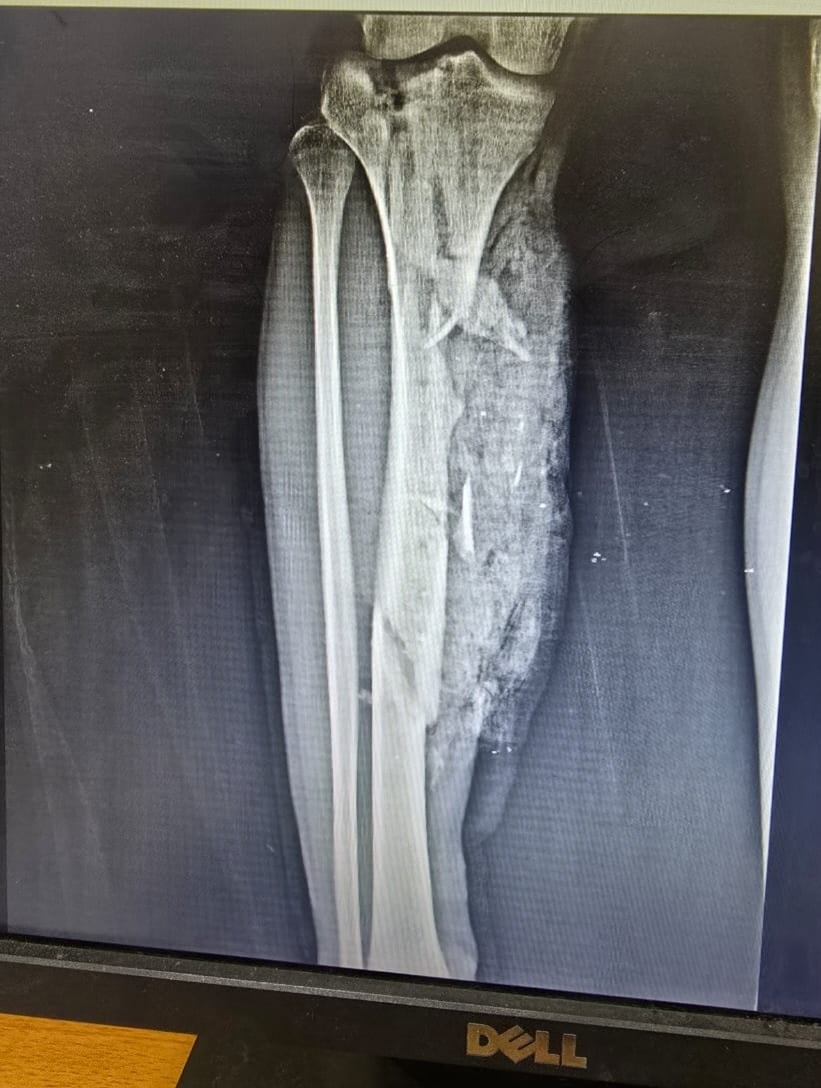

نجح فريق جراحي بمستشفى قها التخصصي، التابعة لأمانة المستشفيات المتخصصة بوزارة الصحة، بمحافظة القليوبية، في إنقاذ حياة شاب في الـ20 من عمره، اصطدم به قطار، وكاد الحادث أن يودي بحياته، وتسبب في إصابته بكسر متفتت مفتوح مع فقد جزء من العظام بالعضد الأيمن مع قطع بالعضلات، وكسر متفتت مفتوح مع فقد جزء من العظام بالساق الأيمن مع قطع بالعضلات، وتهتك بالقدم اليمنى وقطع بالأوتار والعضلات، مع كسر بعظام القدم.

وتابعت المستشفى، أنه تم تجهيز المريض ولياقته من قسم التخدير وتحضيره وتجهيز الدم والبلازما اللازمة للحالة، حيث استقر التشخيص علي كسر متفتت مفتوح مع فقد جزء من العظام بالعضد الأيمن مع قطع بالعضلات، وكسر متفتت مفتوح مع فقد جزء من العظام بالساق الأيمن مع قطع بالعضلات، وتهتك بالقدم اليمنى وقطع بالأوتار والعضلات، مع كسر بعظام القدم.

وأشارت، إلى أنه بدأت العملية قبل سطوع الشمس ليأتي يوم جديد ببارقة أمل وحياة تولد من جديد بفضل الله ورعايته، وتم عمل توصيل الأوتار والعضلات المتهتكة وتثبيت الكسور باستخدام مثبتات خارجية مع مسامير مجوفة وأسلاك معدنية، وسط تهديد واضح ببتر الساق لسوء حالة الجرح، ولكن جهود الفريق الطبي كان لهم رأي آخر واستطاعوا أن يعبروا بالشاب لبر الأمان.

كسور بجسم الشاب بعد الحادثكسور بجسم الشاب بعد الحادث

الأشعة الخاصة بالمريضالأشعة الخاصة بالمريض